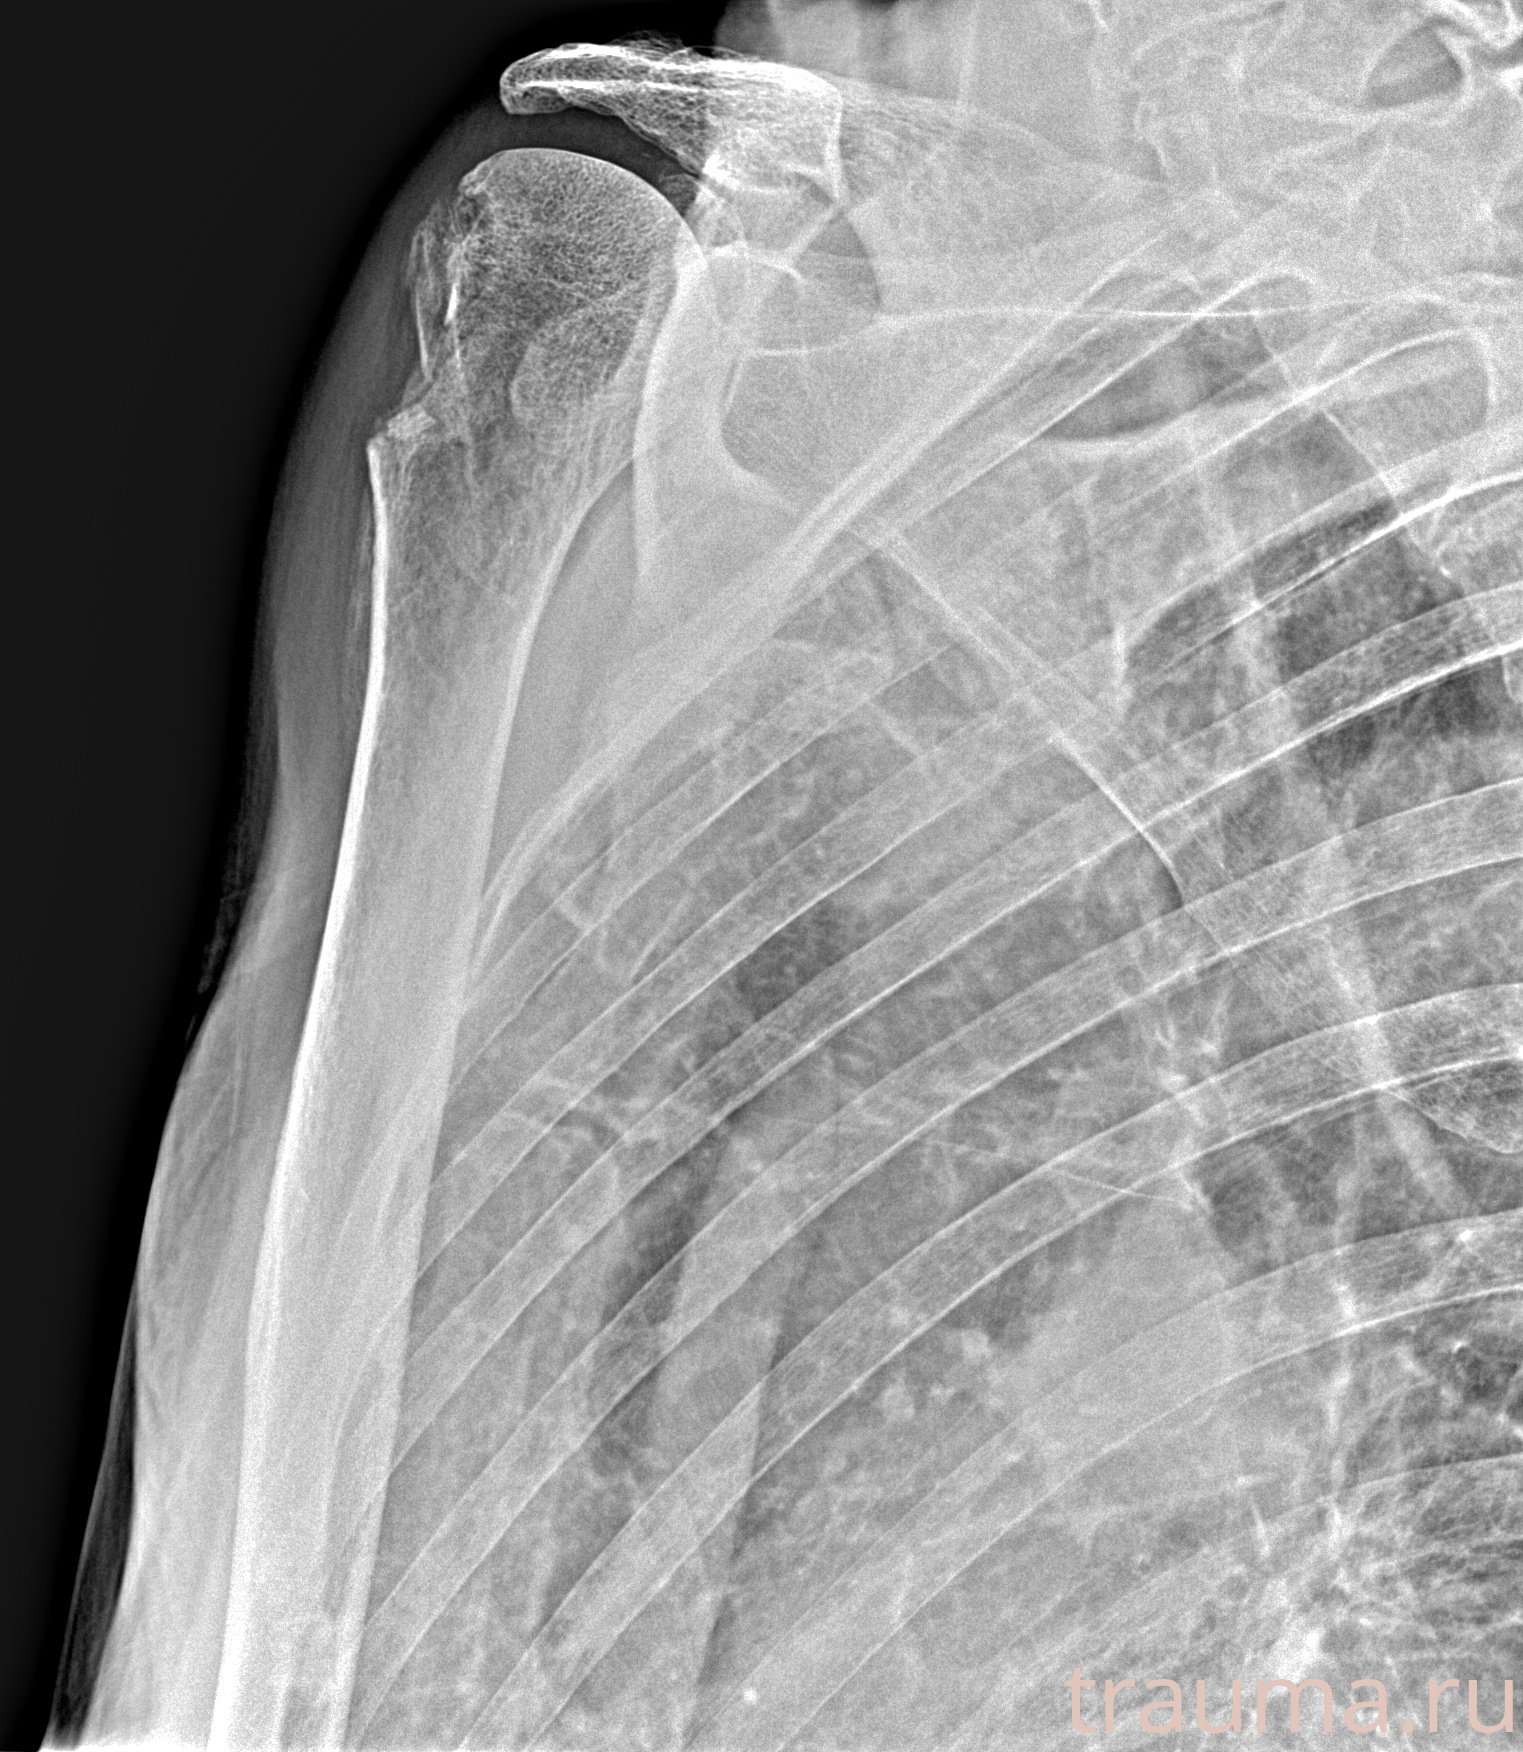

Рентгенограммы

Рентген на дому: по вашему адресу приезжает врач-рентгенолог, травматолог-ортопед с мобильным рентгеновским аппаратом, проводит диагностику травмы или заболевания, делает необходимые рентгенограммы, дает рекомендации по дальнейшему лечению. Получить качественные снимки в домашних условиях возможно благодаря уникальной методике, разработанной МосРентген Центром для института  Склифосовского